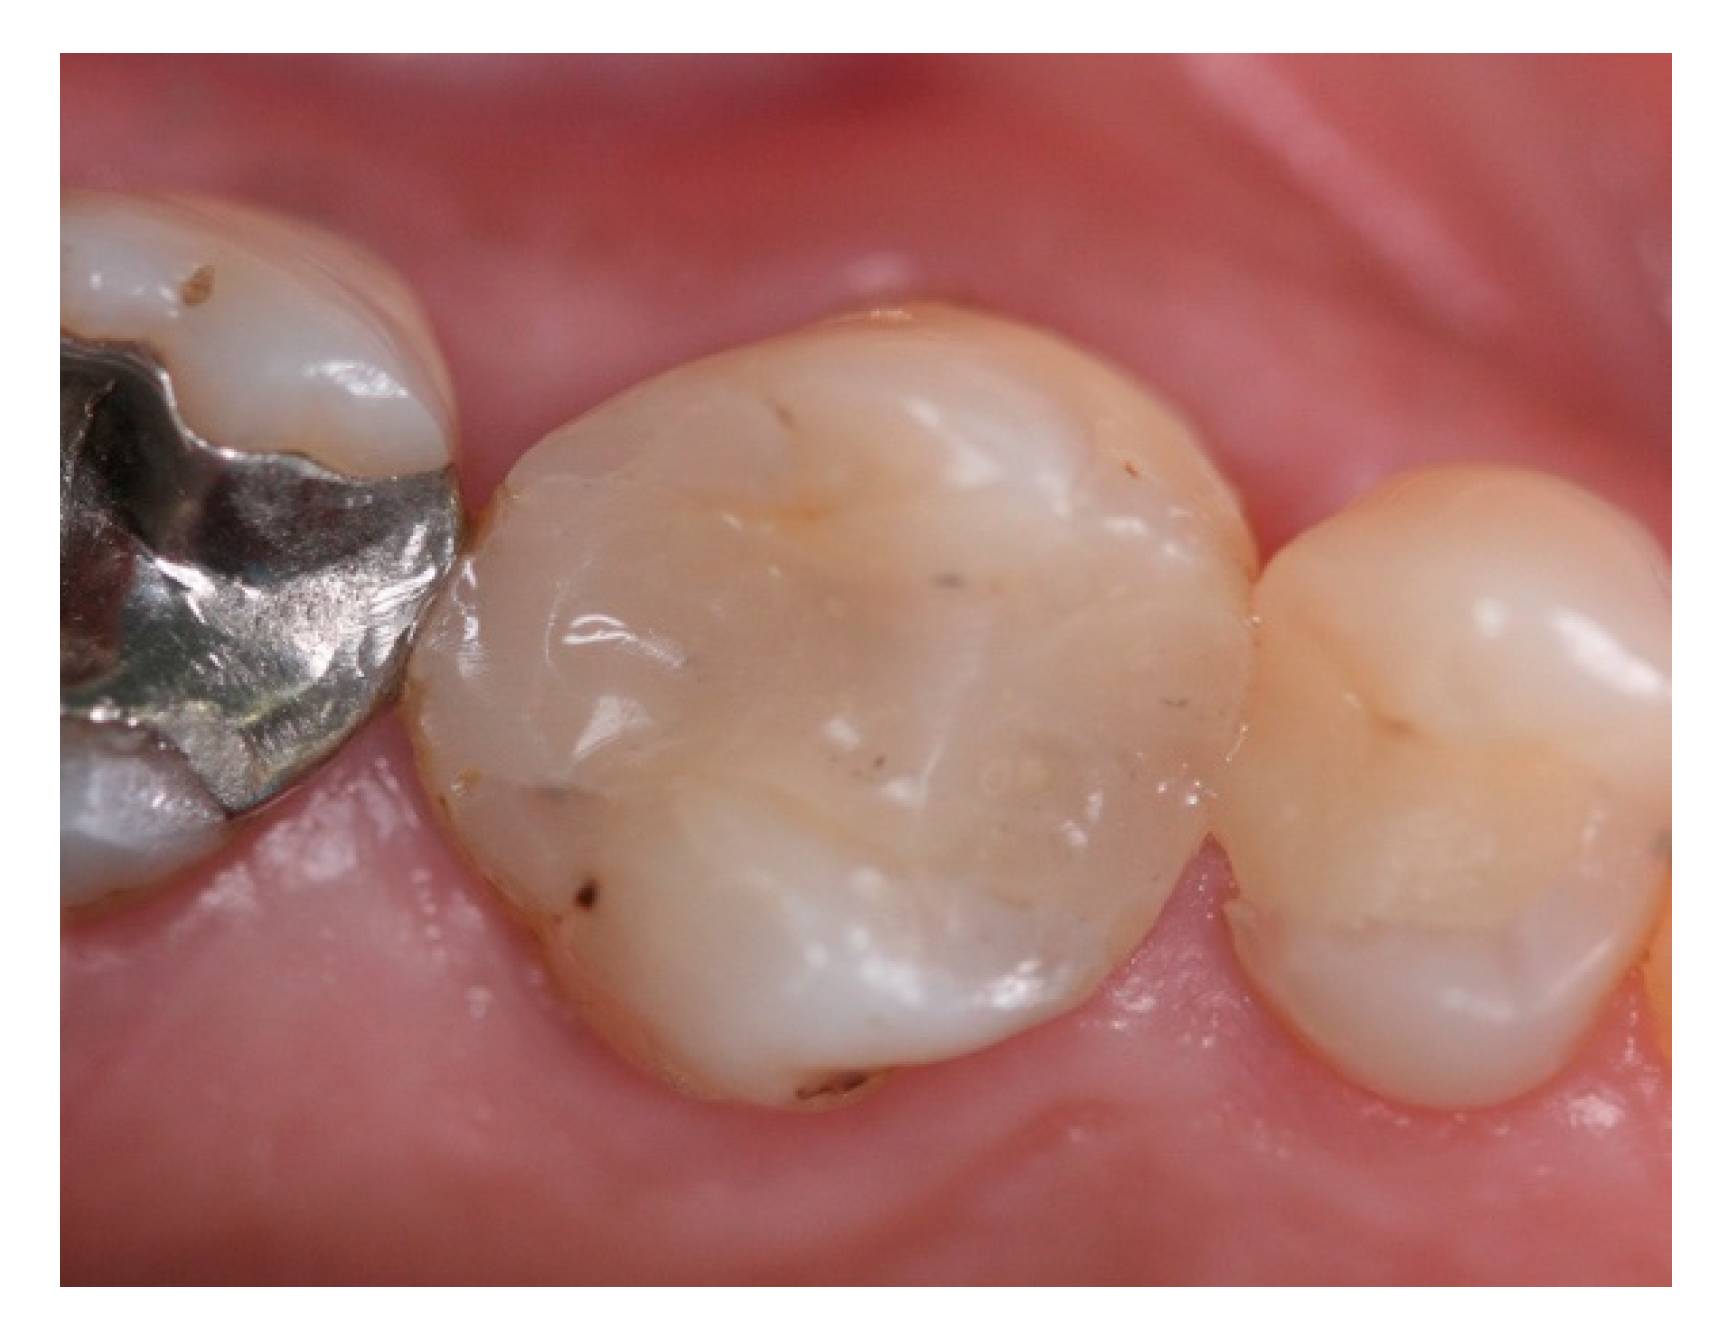

- Bleyan, S.; Gaspar, J.; Huwais, S.; Schwimer, C.; Mazor, Z.; Mendes, J.J.; Neiva, R. Molar Septum Expansion with Osseodensification for Immediate Implant Placement, Retrospective Multicenter Study with Up-to-5-Year Follow-Up, Introducing a New Molar Socket Classification. J. Funct. Biomater. 2021, 4, 66. [Google Scholar] [CrossRef] [PubMed]